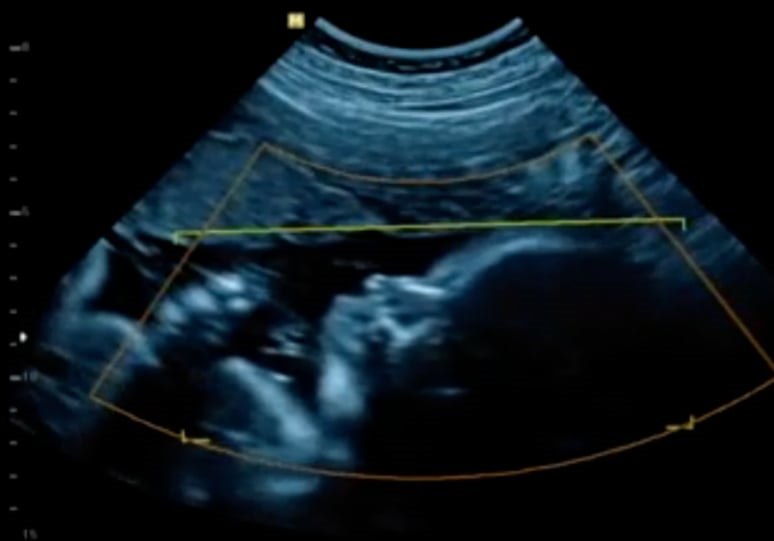

Una procedura assai complessa eseguita dall'équipe della Clinica Ostetrica e Ginecologica dell'ospedale di Chieti diretta da Marco Liberati, ha strappato a un destino già segnato una bimba che alla 24esima settimana ha manifestato l'insorgenza di una rarissima forma di anemia, dovuta alla presenza di una molecola, l'antigene Kell, sui suoi globuli rossi. Si tratta di una patologia rarissima che non porta quasi mai ad anemizzare il feto, ma quando accade si presenta con caratteri di estrema gravità, con esito mortale.

"Abbiamo ingaggiato una lotta contro il tempo - spiega Francesco D'Antonio, responsabile del Centro di medicina prenatale e professore all'Università D'Annunzio - perché era urgente fare una trasfusione in utero, procedura rischiosa a poche settimane di vita, resa ancor più complessa dalla necessità di utilizzare un determinato tipo di sangue adatto alla piccolina. Ci siamo comunque riusciti, grazie alla collaborazione degli immunoematologi del nostro Centro Trasfusionale Amalia Procida e Alessandro Gigante, e abbiamo potuto eseguire la trasfusione, al termine della quale lei ci ha regalato quel sorriso che ci ha emozionati profondamente, segno della sensazione di benessere provata".

Ma si rendeva necessario un supplemento di 'expertise per mettere in sicurezza la bimba e soprattutto i suoi globuli rossi, a rischio di essere distrutti dagli anticorpi. Così a essere trattata è stata la mamma, sottoposta a plasmaferesi in Nefrologia, una procedura che permette di separare il plasma dal sangue per rimuovere dal circolo sostanze nocive. Ci sono volute 10 sedute, 4 trasfusioni in utero e monitoraggio costante per portare avanti la gravidanza e far venire alla luce la piccola alla 34esima settimana.

"Questa bambina è stata salvata grazie all'alta specializzazione sviluppata a Chieti nella medicina prenatale - sottolinea Francesco D'Antonio - che ci permette di seguire con successo le gravidanze complicate e a rischio, grazie a un team multidisciplinare su cui possiamo contare e al Direttore Liberati che supporta con piena fiducia l'innovazione e l'introduzione di metodiche utilizzate in pochissimi centri. Abbiamo restituito la gioia della maternità a una donna già provata, in anni lontani, dalla perdita del suo bambino per la stessa patologia, che all'epoca non era stata riconosciuta e trattata. Ai colleghi che hanno permesso tutto questo, Barbara Matarrelli, Danilo Buca, Luciano Di Tizio, Diego Gazzolo Direttore della Neonatologia e Lorenzo Di Liberato, va la mia gratitudine per il risultato che tutti insieme abbiamo ottenuto, e quella della bambina che abbiamo strappato a un destino che sembrava già scritto".